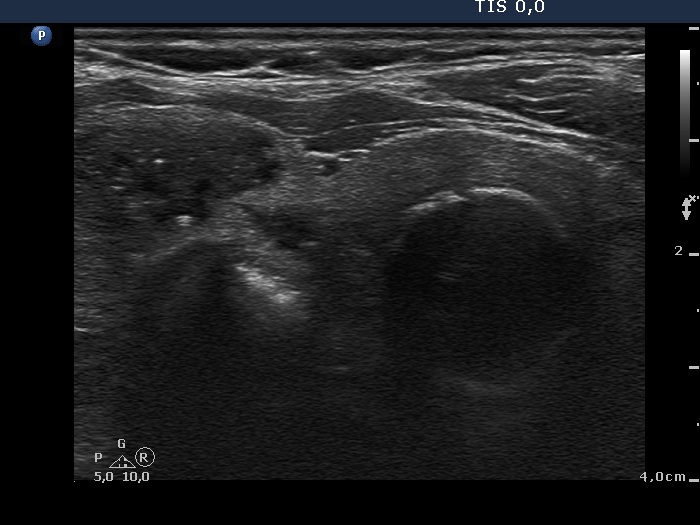

Ultrasonography. The thyroids were composed of multiple nodules with different echogenicities. The lesion presented various forms of intranodular hyperechogenic figures, including microcalcifications. Despite the presence of the latter, neither of the lesions were suspicious, they presented regular and sharp borders. increased intranodular blood flow.

Cytology was performed form two lesions and resulted in benign colloid goiter and benign follicular proliferation. The images of the latter smear are demonstrated which was gained from a moderately hypoechogenic nodule in the left lobe.